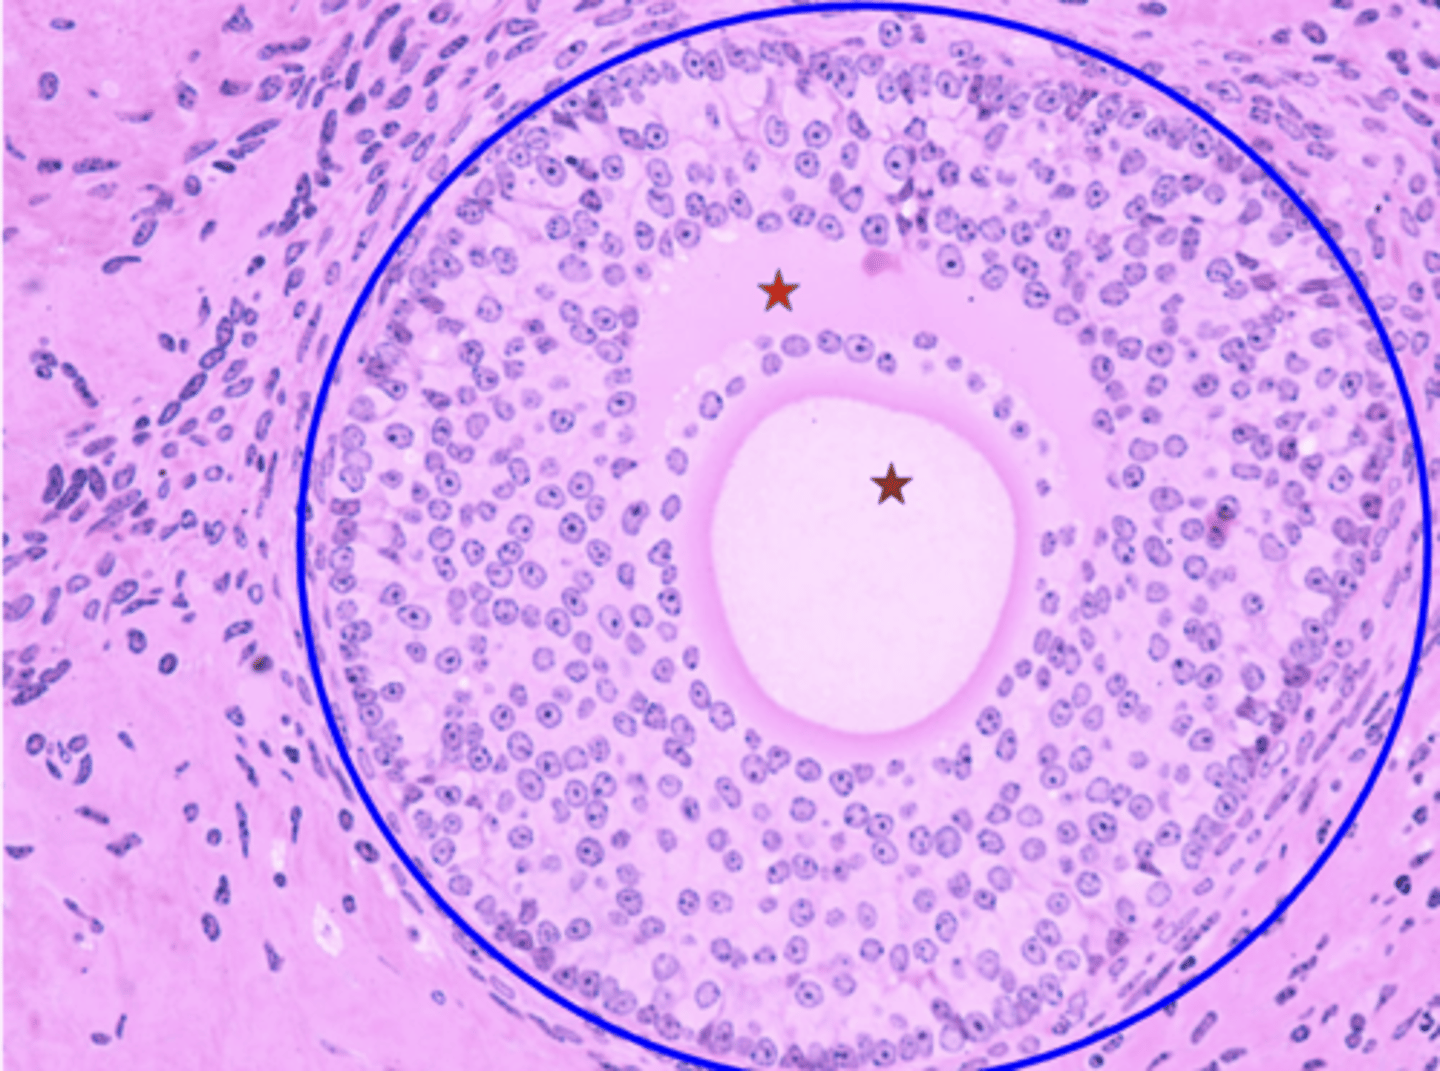

Seminiferous tubule

What is the green outline?

Spermatogonium

What is the black arrow?

Primary spermatocyte

What is the red arrow?

Spermatid

What is the blue arrow?

Spermatozoon

What is the purple arrow?

Interstitial cells

What is the pink outline?